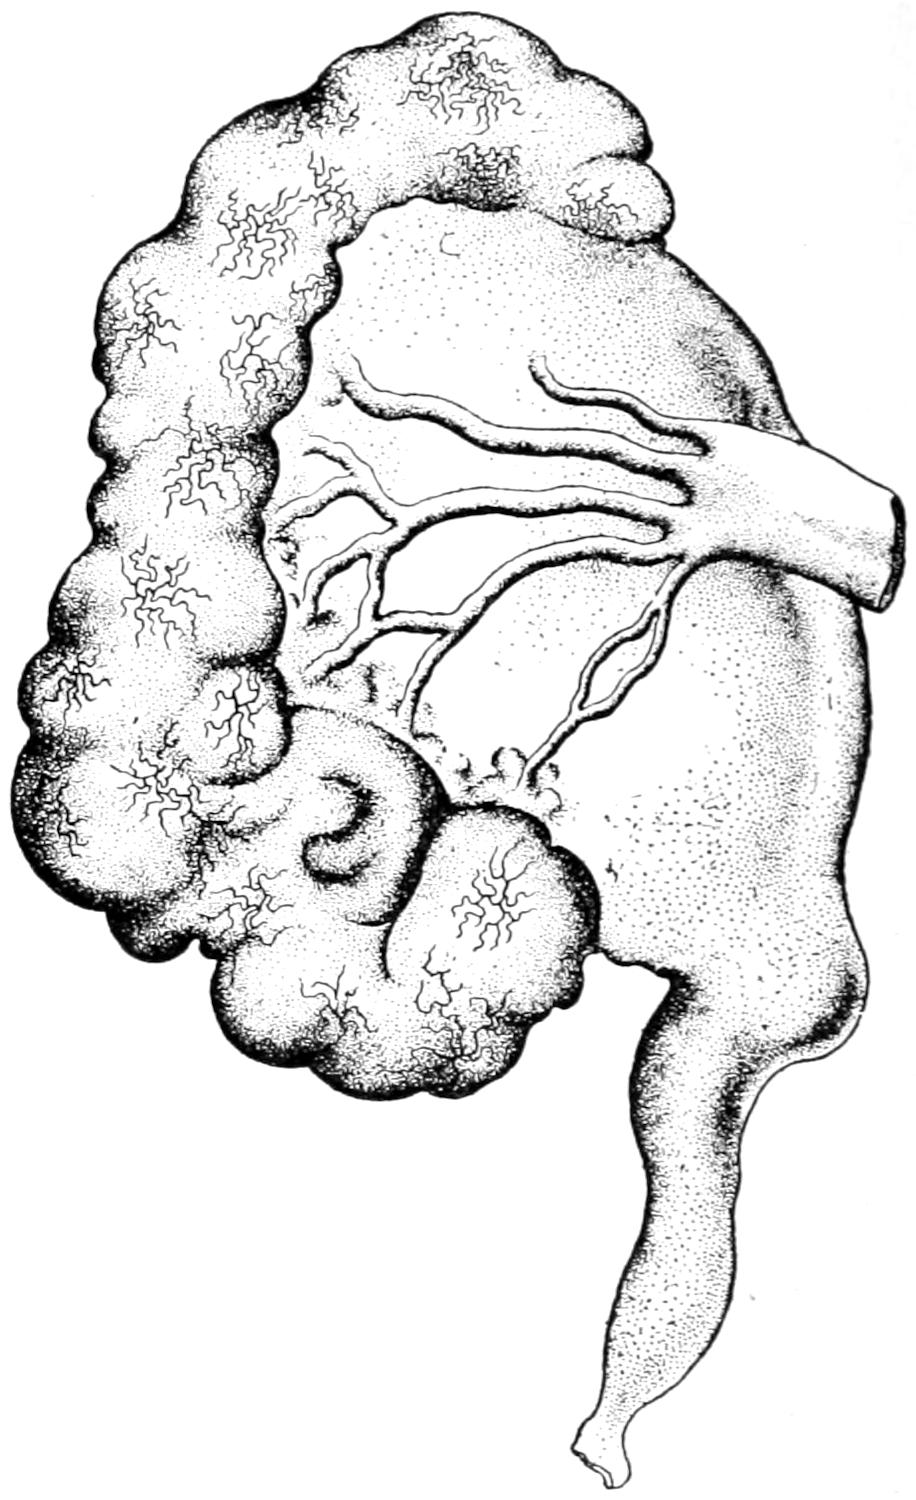

THE APPENDIX AND ITS DISEASES 851

CHAPTER L.

THE LARGE INTESTINES AND THE RECTUM 869

CHAPTER LI.